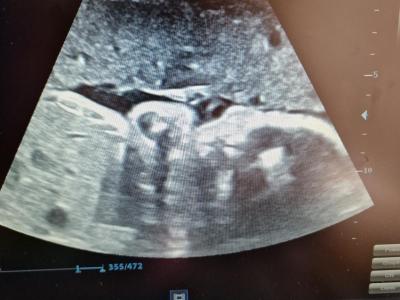

14. April 2025We extend our heartfelt thanks to all our sponsors and friends who made this possible, also thanks to additional donations. This means we can offer prenatal care as usual, as well as echocardiograms and Doppler ultrasounds.